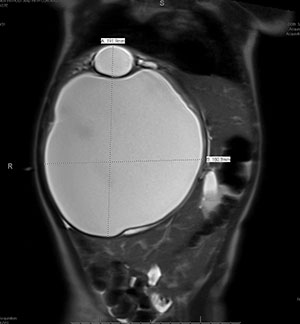

An abdominal x-ray was performed, which showed striking hepatomegaly. Ultrasound demonstrated a multicystic mass (17.7 x 16.3 x 12.6 cm) in the right upper quadrant with thick septations and internal debris. MRI revealed mass effect on the adjacent structures, including upward displacement of the right hemidiaphragm and compression of the right kidney (Figures 1 and 2).